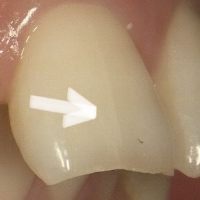

症例3

治療方法 ラミネートベニア法

治療期間 2ヶ月

治療費用 ラミネートベニア 1歯 ¥154,000×3 ¥462,000(税込)

治療の副作用.リスク 歯を削る必要がある

歯ぎしりや食いしばり癖があると欠けることがある

ラミネートベニア法

前歯の表面のヒビが目立つこと、前歯の先端の形がギザギザしている部分がお悩みでした。

前歯のヒビは、レジンの劣化により歯との境目に段差ができていることが原因です。

前歯の形と表面のヒビを完全にカバーして質感を整える場合はラミネートベニアがおすすめです。着色しにくく長期的に綺麗な状態を保つことができます。